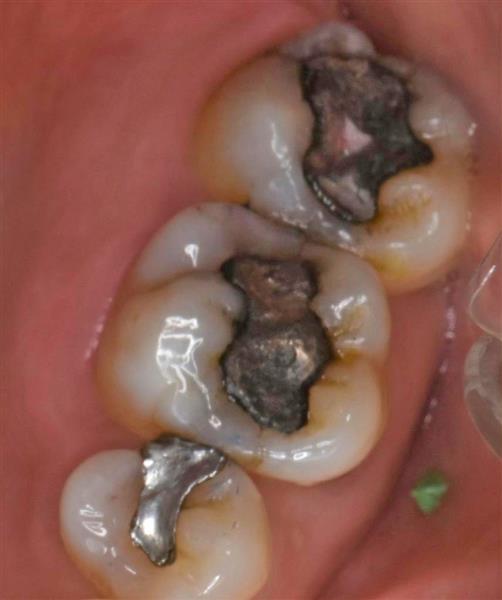

左は、アマルガム修復です。

右はインレー修復(金銀パラジウム合金)と呼ばれる一般的な詰め物です。

上2つはアマルガム修復です。

一番下の小臼歯は、インレー(金銀パラジウム合金)です。

アマルガムだけ、少し黒っぽいのが分かります。